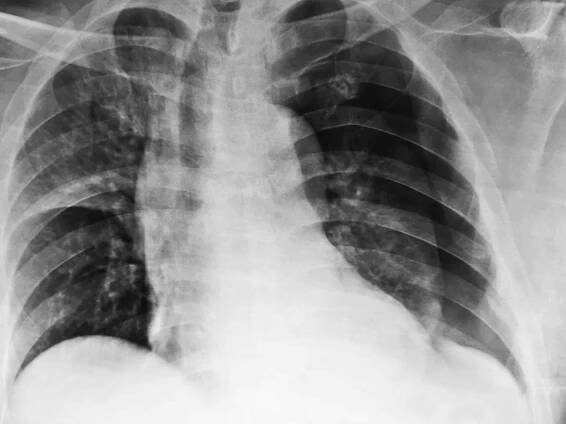

Rentgenový snímek – pneumotorax levé plíce a nahromadění vzduchu v pleurální dutině hrudníku (bílá barva). Zdroj: Getty Images